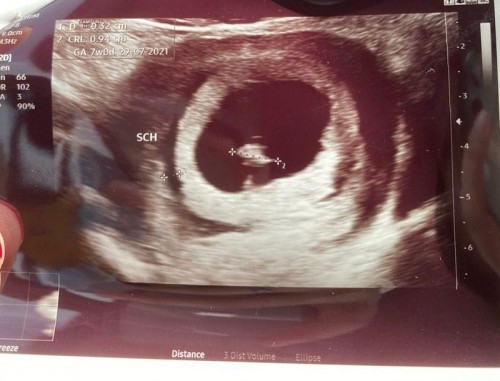

Pendarahan dekat rahim (sch)

Salam, sy baru lepas scan and doctor detect ada pendarahan dekat rahim. Tapi sy takda bleeding & sakit perut. Baru 7weeks. Ada sesiapa pernah mengalami? Boleh share tq #subchorionic hemorrhage #advicepls